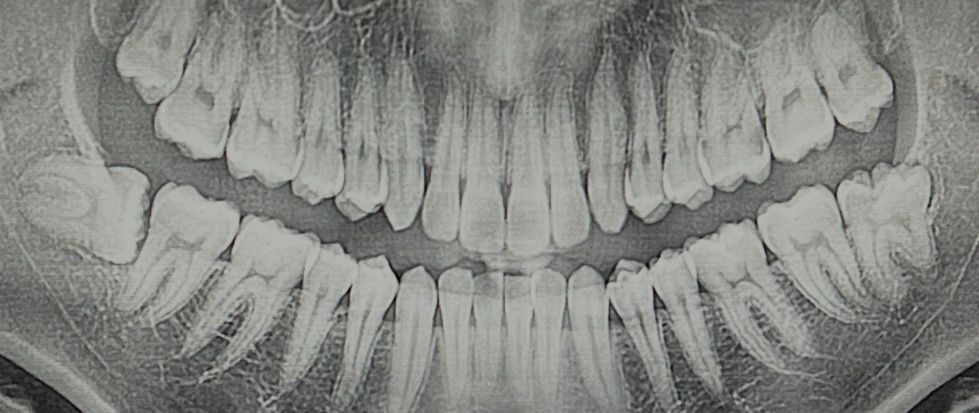

충치치료 했을때 치아 사진인데 양옆에 사랑니가 있습니다.

통증은 따로 없는데 요즘따라 이물질이 낍니다.

이럴때는 사랑니를 발치해야 할까요?

• 1번 째 사진